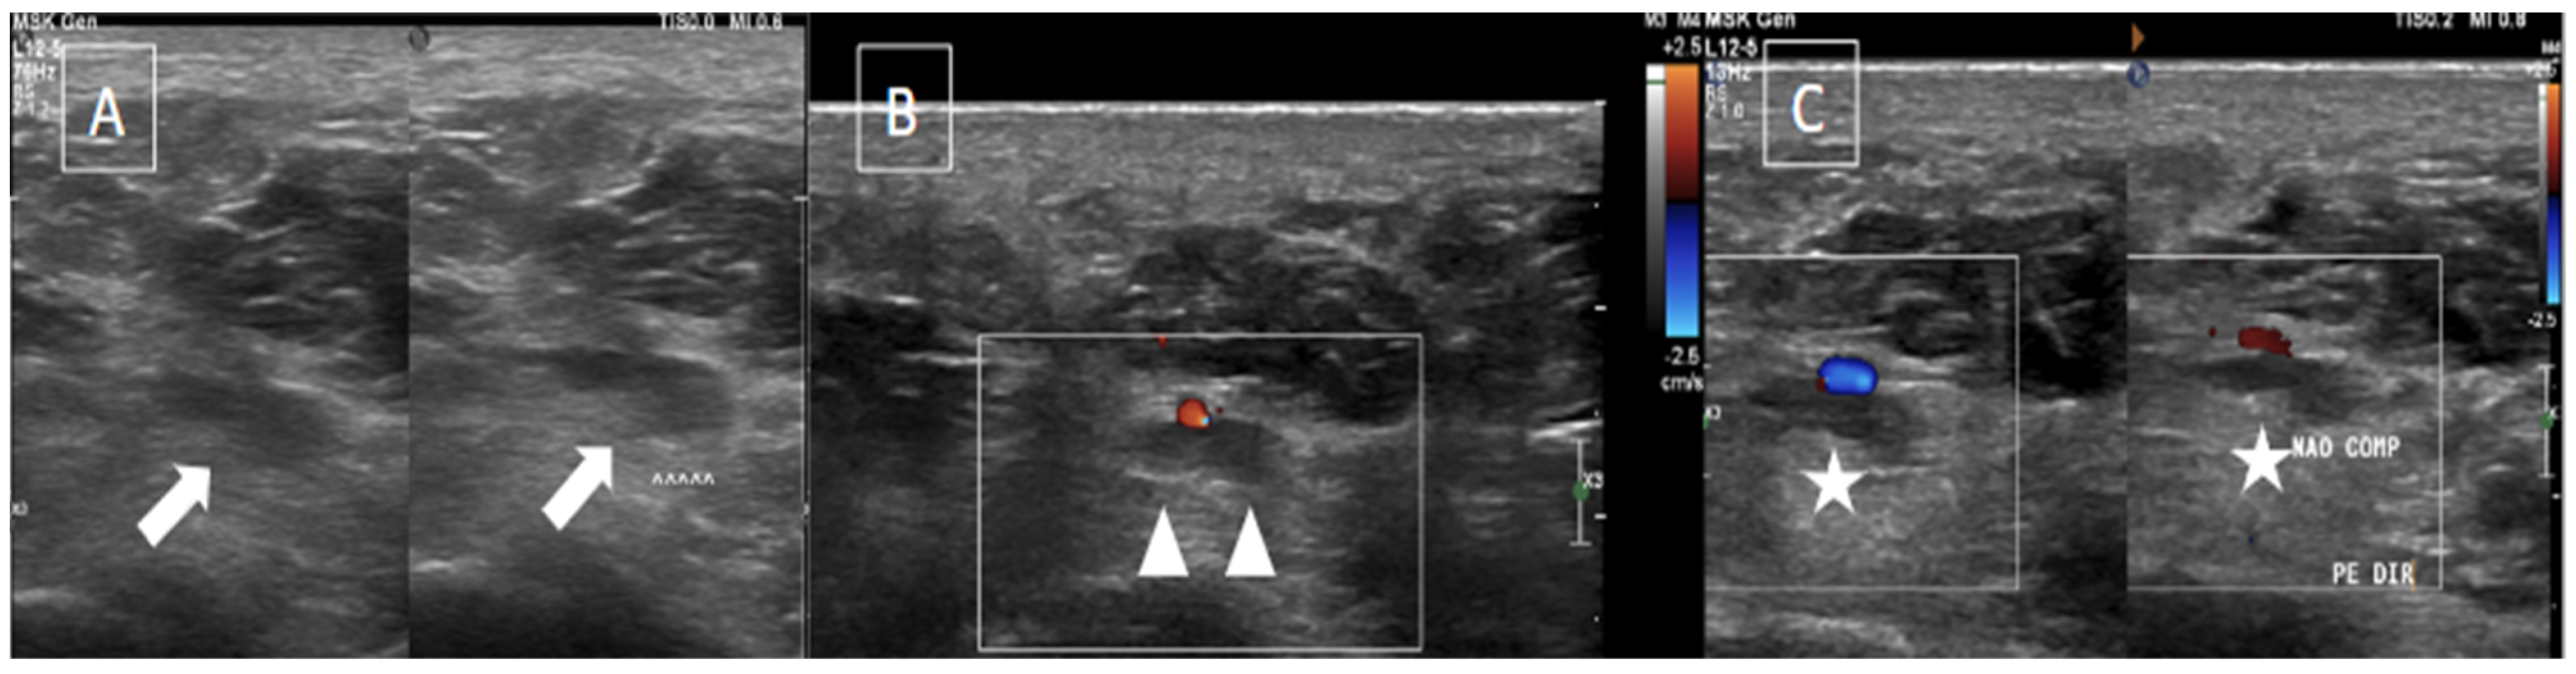

| Perivascular edema and enhancement Muscle edema Intraluminal signal change Venous enlargement Presence of collateral veins Venous filling defects (post-gadolinium injection) | Local tenderness Loss of compressibility Venous enlargement Intraluminal content Perivascular edema | Local tenderness Loss of flow Filling defects |